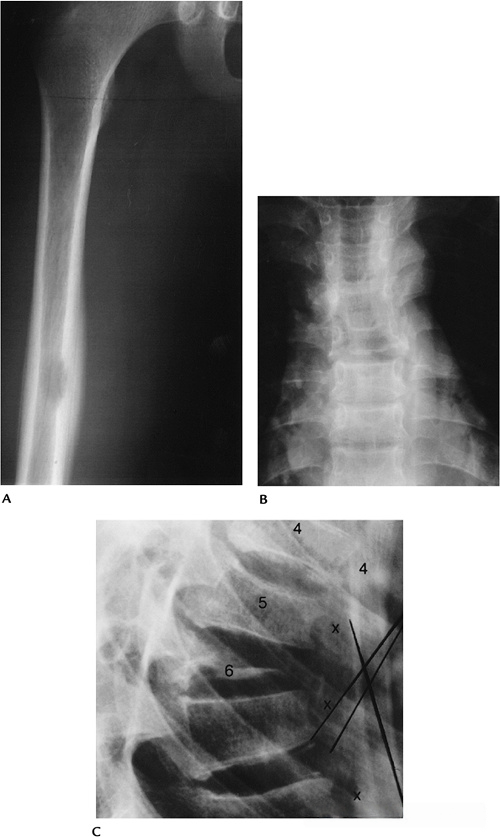

80390c30023905a3a790841455d25218.png

图-11骨髓纤维化。(A)胸部X光片显示骨密度增加和明显脾肿大。(B)骨盆X光片显示散在的骨硬化。腰椎前后位(C)和侧位(D)X光片显示骨密度增加。

908f8e2204e85c218c67070fbae696ae.png

图-12骨髓纤维化。股骨的T1像显示低信号度,除了远端。